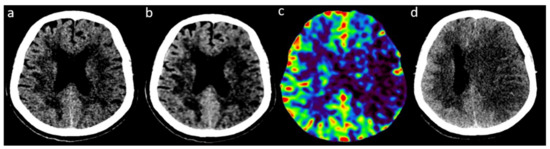

2.2. Image Acquisition and Reconstruction

2.3. Readings of FIRST-LCD and AIDR3D ASPECTS on Baseline NCCT

2.4. Consensus Readings of Final and rCBV ASPECTS